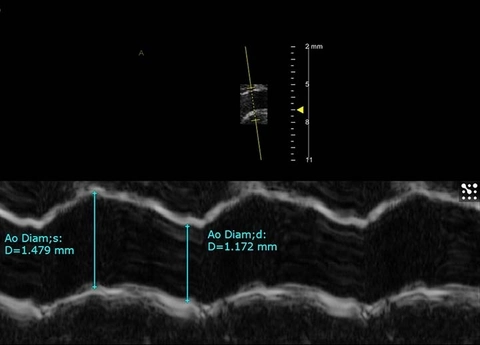

Anatomical M-Mode of mouse aorta with diameter measurements.

AM-Mode has been improved by the "fully digital” offering of high temporal resolution. Thus, AM analysis can be performed in any direction, as a uni-dimensional echocardiogram. AM-Mode is also commonly used for the accurate measurements of vessel wall thickness, intima media thickness, ventricular walls and volumes of the cardiac chambers.